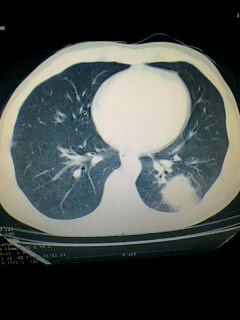

标题: CT28315:咳嗽咳痰咯血半月并胸痛 [打印本页]

标题: CT28315:咳嗽咳痰咯血半月并胸痛

左下肺肿块影,深分叶,考虑肺癌。

不排除左肺下叶周围型肺癌可能!建议穿刺活检!

考虑左肺下叶周围型肺癌。

考虑左肺下叶周围型肺癌并阻塞性肺炎。